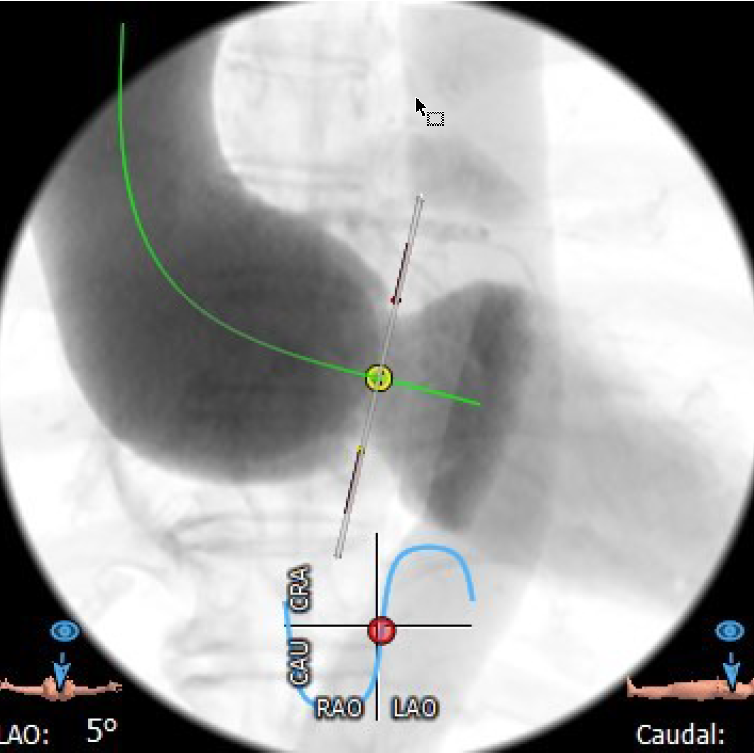

4.患者术中造影角度LAO:5°,CAU:3°。

最佳投照角度:LAO:5°,CAU:3°

经右侧股静脉置入临时起搏器,经右侧股动脉在患者主动脉无冠窦内放置1根6F猪尾导管协助定位。透视下定位后第五肋间小切口进胸,打开心包,选择心尖裸区缝制六边形荷包。心尖穿刺后将泥鳅导丝过主动脉瓣经升主动脉、主动脉弓到达降主动脉膈肌水平(图1),通过TEE确认细导丝没有与二尖瓣腱索缠绕。单弯管交换硬导丝后(图2、图3),用16F扩张鞘预扩心尖穿刺处,后将 J-Valve瓣膜(29mm)装入输送器。将输送器推送至主动脉根部,释放定位件,适当调整定位件角度使其进入三个主动脉窦部,并通过DSA和TEE确定三个定位件准确入窦后完全释放瓣膜,撤出输送器(图4)。通过DSA和TEE观察人工瓣膜膨胀后金属支架的形态、位置良好,无瓣周漏,收缩期左室侧反流消失(图5、图6)。撤出导丝,收紧心尖处荷包线并打结,后鱼精蛋白中和肝素,彻底止血,逐层关胸,封皮,拔出股动脉鞘并在股动脉穿刺处压迫止血。手术过程顺利,患者生命体征平稳。

图3 主动脉瓣大量反流;主动脉瓣环平面几乎与脊柱平行